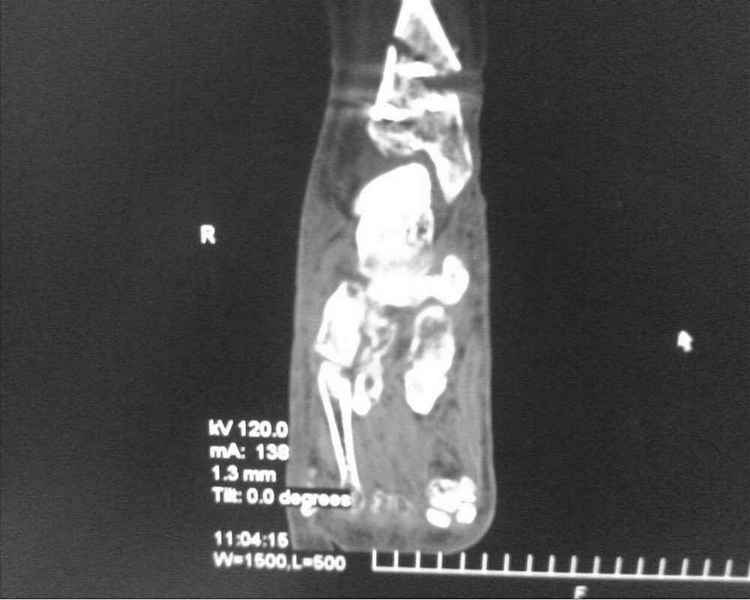

[Ortho] [1/2] Метатарзал краш синдром в порочном сращении (эквинусная стопа), несращение сегментарного перелома костей голени после БИОС , ПТФБ, ХВН СЕАР С-6.

Больной 39 лет. Травма получена в ДТП 21.09.09г. был госпитализирован в обл. больницу

соседней области с диагнозом сочетанная травма зчмт сотрясение головного мозга

сегментарный перелом костей правой голени с\3-н\3, суральный флеботромбоз циркулярные

некрозы н\3 правой голени правого голеностопного сустава лечение скелетным вытяжением за

пяточную кость. переведён в наше отделение 6.10.09г. возобновлено скелетное вытяжение,

перевязки, иссечение некрозов, антикоагулянты. На уздг диагноз флеботромбоза

подтвержден. 28.10.09 операция БИОС правой б\берцовой кости штифтом PTNL остеомед .

остеосинтез м\берцовой кости не выполняли из-за наличия гранулирующих ран и некрозов в

месте операционного доступа. Вторым этапом планировалось наложить аппарат Илизарова для

выведения стопы из эквинуса и динамизации штифта. Но из-за наличия гранулирующих ран и

некрозов в местах проведения спиц на стопе и голени 19.11.09 переведен в ожоговое отделение

для САДП гранулирующих ран после некрозов. 23.11.09 САДП. В послеоперационном периоде-

длительное заживление ран с лизисом кожных лоскутов, манифестное развитие ХВН с

формированием трофических язв и лимфэдемы. Больной явился на госпитализацию 13.01.10г.

локальный статус и свежие снимки прилагаю. Данные уздг выложу позже. Что в этой ситуации

делать я не знаю. Признаков сращения на Rg-нет плюс метафизарный фрагмент кивнул на вальгус.